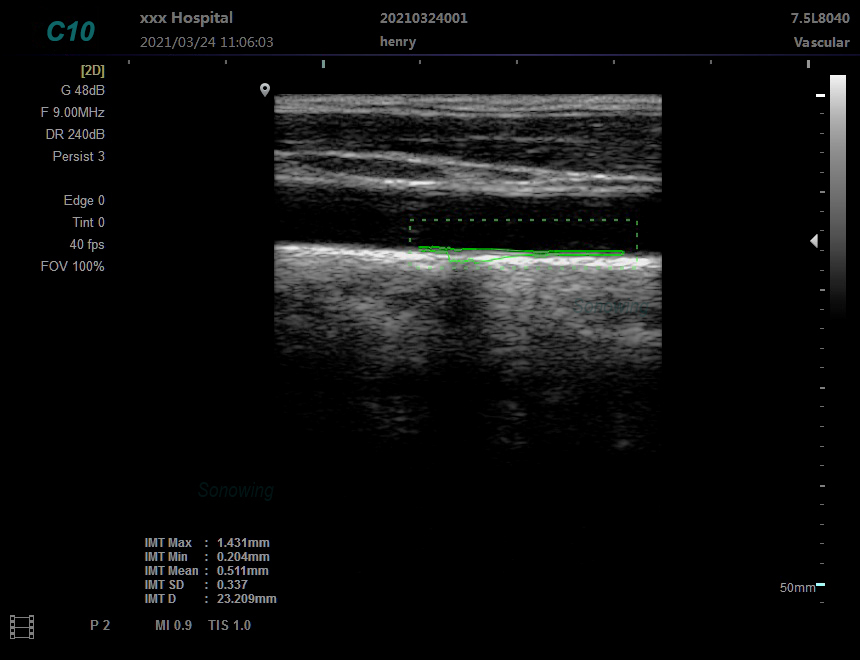

5)Support probe:Convex\Linear\Cavity\Micro-convex\Rectal

6)Display Modes:B,B/B,4B,B+M,M, PW,B+PW

7)Dynamic Range:80~280dB adjustable

8)Gray scale:256 scales

9)Depth display:≥280mm

10)Gain adjusts:8 segments TGC, B/M/D/C is independently adjustable; TGC curve can show and hide automatically

11)B/D dual-purpose:linear array: B/PWD; convex array: B/PWD

12)Acoustic output:Mechanical index and thermal index real-time display

13)Frequency Conversion:Support operating frequency according to the probe application, frequency range:2-12MHz